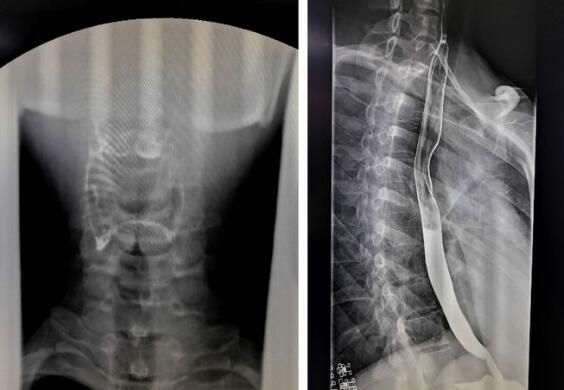

数字化胃肠机拍摄的上消化道造影图

随着数字化胃肠机临床应用越来越广泛,其功能性也大大增强,那么数字化胃肠机到底能做哪些检查呢?其功能你有了解多少?1、上消化道造影,能显示咽部到十二指肠的影像。